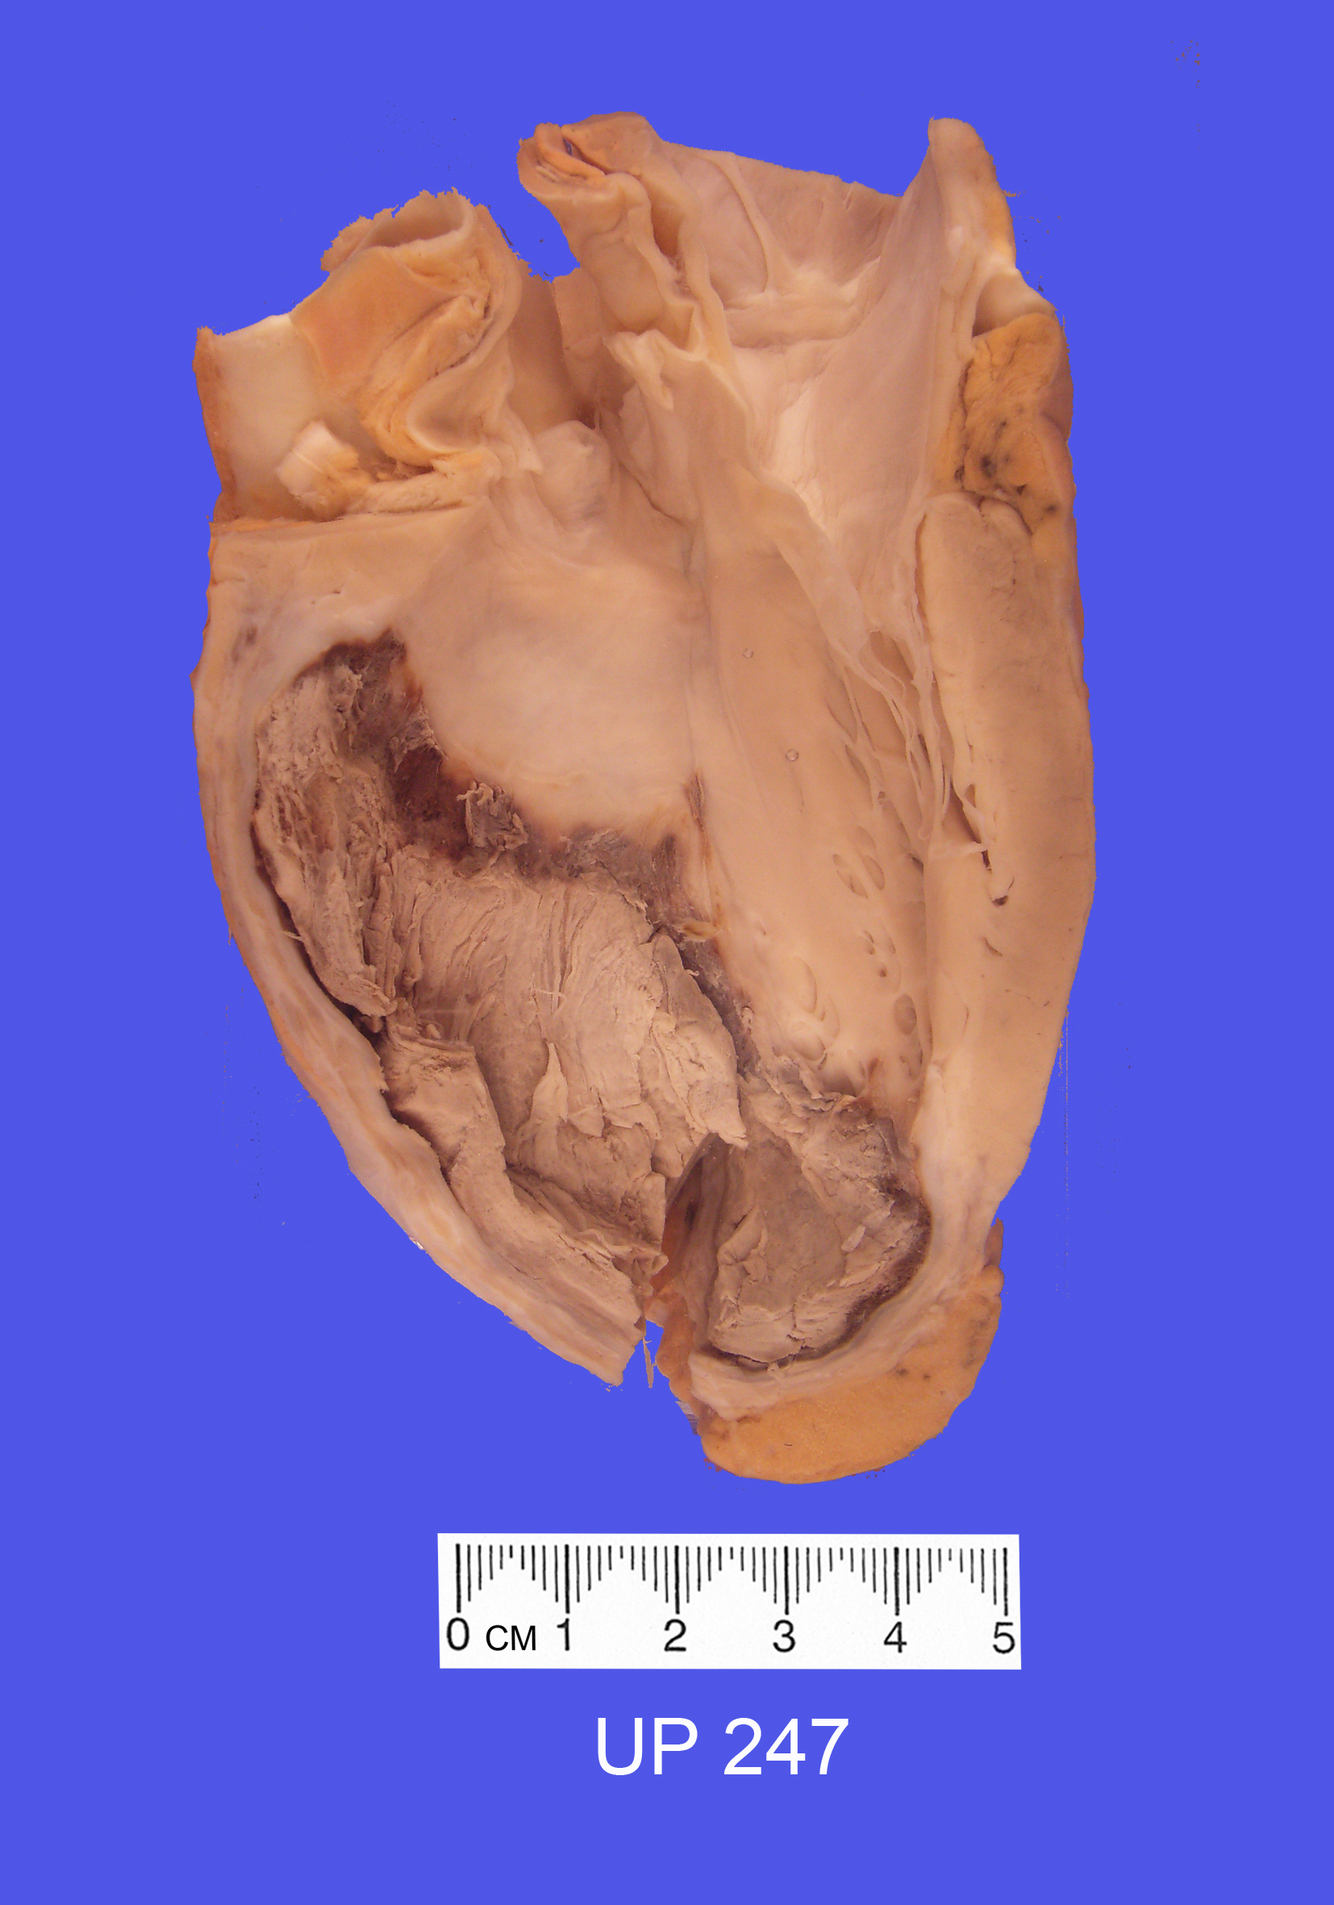

The specimen shows a slice through the left and right ventricles.

A massive recent infarct is present in the anterior, septal and posterior regions of the left ventricle with a slight extension onto the posterior wall of the right ventricle. The necrotic muscle appears pale yellow-grey in colour and reactive hyperaemia is seen at the interface with the viable myocardium. This is the territory of the left anterior descending coronary artery.

A mural thrombus has formed on the anteroseptal infarcted zone.

The anterior and posterior descending coronary arteries can be seen in cross-section in the epicardial fat and they are severely stenosed by atherosclerosis.

Histological sections confirmed a recent infarct, only days old, with loss of cardiac muscle nuclei and intense hyperaemia bordering the infarct.

The postmortem also revealed numerous peripheral pulmonary emboli with an occasional associated infarct and a left calf deep venous thrombosis. A small recent infarct was also present in one kidney.